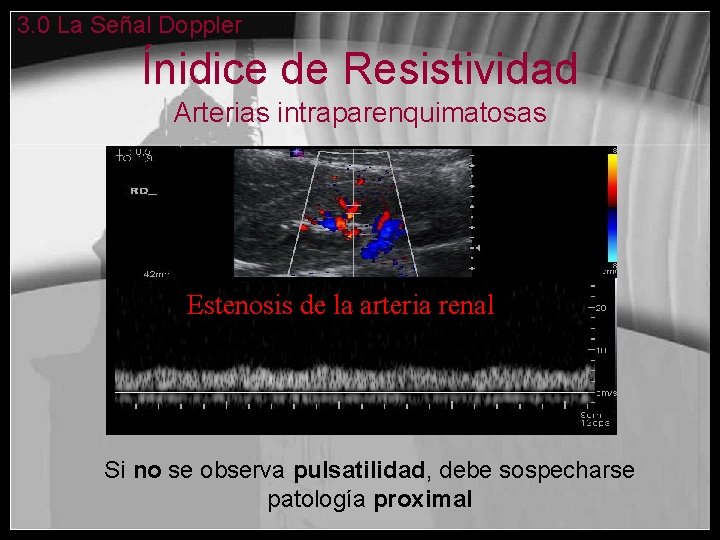

Ínidice de Resistividad Arterias intraparenquimatosas • Es la relación entre la sístole y la diástole (velocidad pico sistólica– veloc. final diastólica/ veloc. pico sistólica) • El ángulo no tiene que ser corregido porque es un cociente • Riñónes – IR Normal : 0, 6 -0, 8 • IR elevado: se observa en edema, vasoconstricción, trombosis venosa… • IR bajo: se observa distalmente a una estenosis (flujo tardus-pardus)

3. 0 La Señal Doppler Ínidice de Resistividad Arterias intraparenquimatosas Normal Además del resultado del IR es importante fijarse en la morfología de la onda

3. 0 La Señal Doppler Ínidice de Resistividad Arterias intraparenquimatosas Estenosis de la arteria renal Si no se observa pulsatilidad, debe sospecharse patología proximal